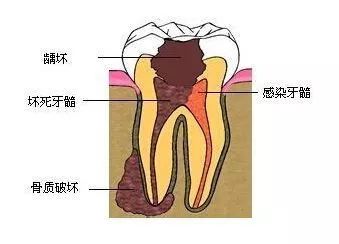

第一係蛀牙會痛,解釋係牙髓受細菌感染,可能已經導致牙髓炎,嗰陣要進行根管治療;

第三係蛀牙引起牙根發炎,牙齦度都會生膿包,醫生會影相檢查症狀。

第三階段:牙齒超過一半爛曬,係話已經重度蛀牙,細菌傷及牙髓牙神經,仲伴隨住劇烈疼痛,牙神經病變就要番啲根管治療處理,拯救滿身傷痕嘅牙齒。

如果唔進行及時治療,病變就會愈來愈大,由淺蛀發展到深蛀,對凍熱酸甜等食物刺激敏感;當損傷到達牙髓,引發牙髓炎,呢個時候牙痛會好嚴重;病變再進一步發展,會引發根尖炎、根尖周膿腫,甚至顎骨骨髓炎,牙齒脫落失位。牙齒出事、冇啦,會影響嚼食,加重胃腸負擔,再者影響身體健康。